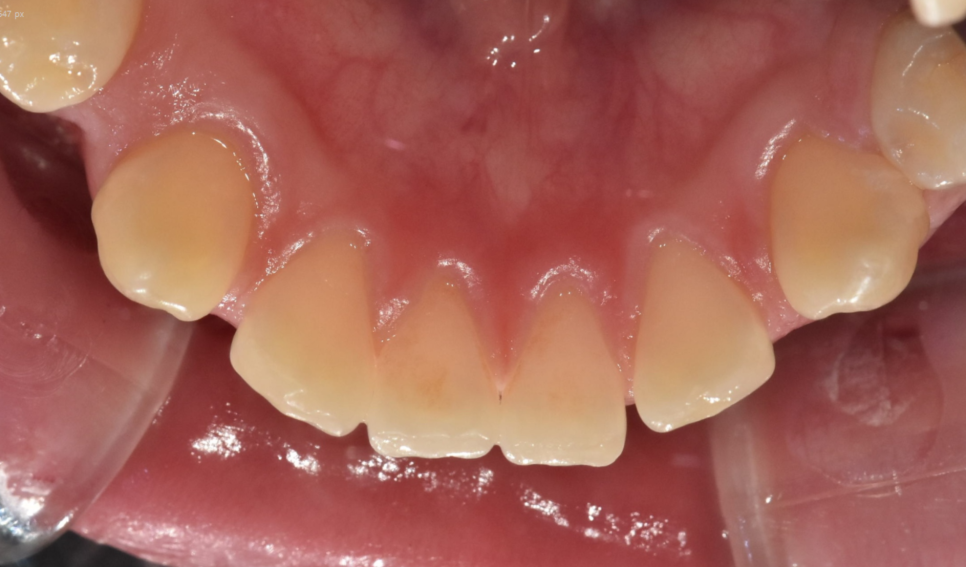

- 발음 기능이 개선됩니다.

벌어진 앞니의 치명적인 단점 중에 하나가

발음이 새거나 어색할 수 있습니다.

벌어진 틈새로 공기가 빠져나가기 때문이죠.

치아 공간 닫힘이 발생하면 발음 개선에도 도움이 됩니다.